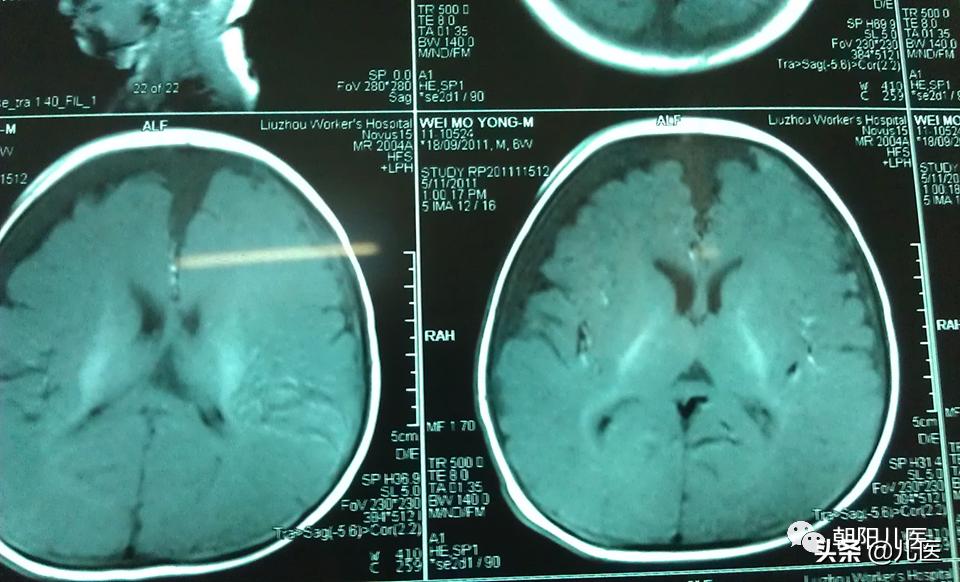

⑤神经影像学:头颅MRI或CT。

硬膜下积液CT